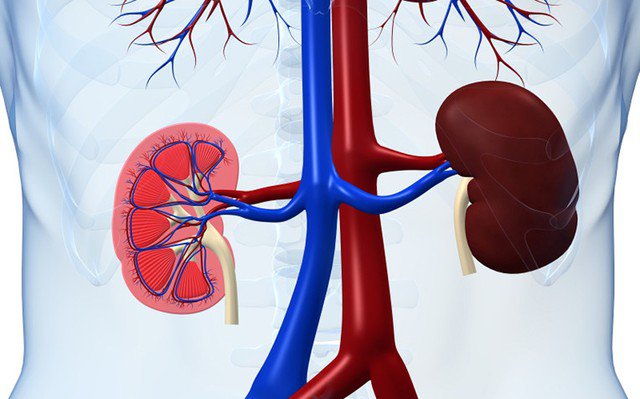

Ảnh minh họa.